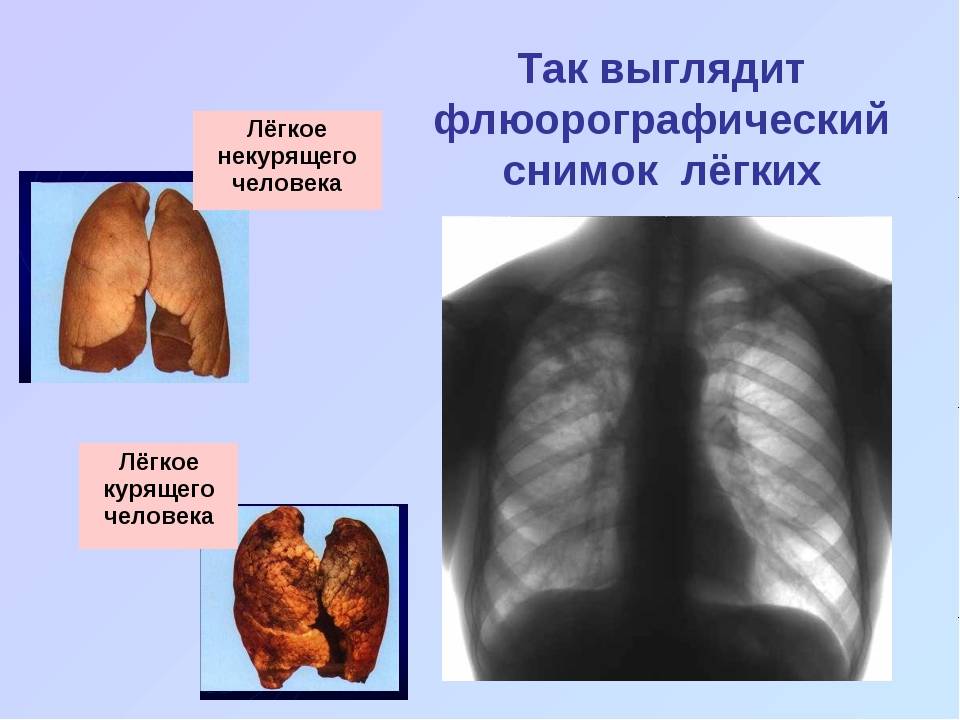

Здоровые Легкие Картинки

Здоровые Легкие Картинки 117 фото